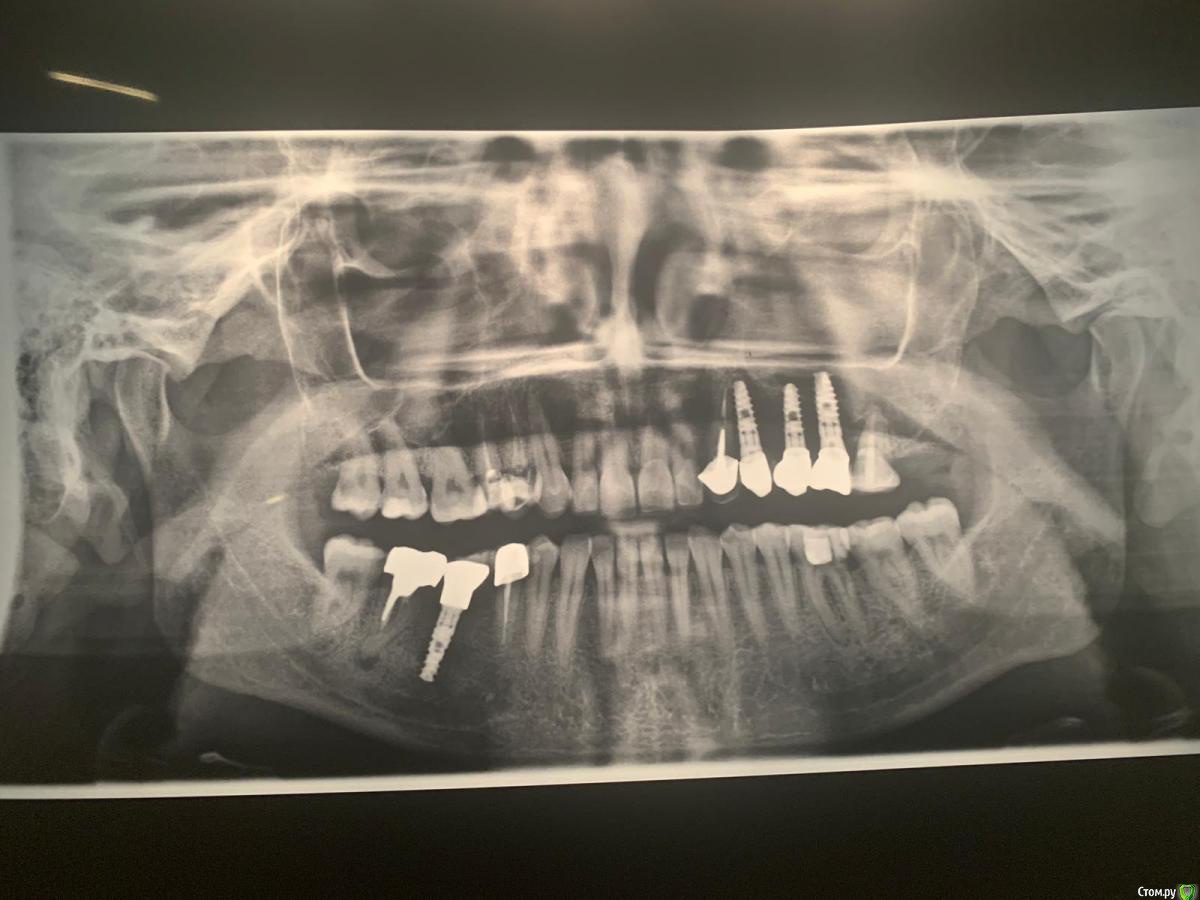

irada Опубликовано 17 декабря, 2019 Поделиться Опубликовано 17 декабря, 2019 Добрый вечер. У меня критическая ситуация. Месяц назад попопала в скорую с температурой и головной болью,выделения из носа не очень обильные но резккий запах, выяснилось -гайморит с левой стороны , сделала курс уколов антибиотиками, но через 2 недели опять поднялась температура и те же самые симптомы , лор отправил делать сникок зубов. У меня как раз с левой стороны подряд 3 импланта сверху , после клыка установлены 3 импланта где жевательные зубы, имланиы были установлены 3 года назад, одновременно с синус лифтингом, врачь говорит что корни имплантов воспалены, вернее кость, там хроническое воспаление, которое вызывает гаймлрит и нужно удалять импланты , чистить, наращивать кость, через время делать новые.Если ли какие то альтернативы? или нет шансов сохранить имплант? Ссылка на комментарий

Bier Опубликовано 18 декабря, 2019 Поделиться Опубликовано 18 декабря, 2019 что-то по этому снимку и кости то вокруг имплантатов не видно, очень плохое качество.Сделайте дентальную компьютерную томографию верхней челюсти, чтобы туда вошли пазухи с соустьями.Но что-то мне подсказывает, что там все на удаление. Ссылка на комментарий

irada Опубликовано 21 декабря, 2019 Автор Поделиться Опубликовано 21 декабря, 2019 вот все что у меня есть, один из снимков сделан после 6 месяцев после имплантацииб там где коронок пока нет. дело в том что я студенка я нахожусь в заграницей и моя кт у врача Ссылка на комментарий

irada Опубликовано 21 декабря, 2019 Автор Поделиться Опубликовано 21 декабря, 2019 что-то по этому снимку и кости то вокруг имплантатов не видно, очень плохое качество.Сделайте дентальную компьютерную томографию верхней челюсти, чтобы туда вошли пазухи с соустьями.Но что-то мне подсказывает, что там все на удаление.мне точно пока не могут сказать нужно ли удалять, сказали может придется как то восстанавливать мембрату потому что имлант пробил синус. и что у меня кость гниет. что надо отрезать кусочек корня импланта восттанавливать мембрану. наращивать кость. но при этом не удалять имплант. я просто первый раз о такой операции слышу Ссылка на комментарий

Bier Опубликовано 24 декабря, 2019 Поделиться Опубликовано 24 декабря, 2019 вот все что у меня есть, один из снимков сделан после 6 месяцев после имплантацииб там где коронок пока нет. дело в том что я студенка я нахожусь в заграницей и моя кт у врачапо этим снимкам криминала нет. Ссылка на комментарий

Bier Опубликовано 24 декабря, 2019 Поделиться Опубликовано 24 декабря, 2019 мне точно пока не могут сказать нужно ли удалять, сказали может придется как то восстанавливать мембрату потому что имлант пробил синус. и что у меня кость гниет. что надо отрезать кусочек корня импланта восттанавливать мембрану. наращивать кость. но при этом не удалять имплант. я просто первый раз о такой операции слышу такую операцию можно сделать. По этому снимку возможно вообще ничего делать не нужно. Нужно посмотреть на КТ. Но повторюсь, ничего криминального нет. Ссылка на комментарий